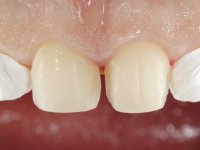

Paciente do sexo masculino, com 36 anos, não fumador. Fez tratamento ortodôntico e reabilitou esteticamente o sector anterior com restaurações em resina composta. As restaurações apresentavam um aumento vertical médio de 2 mm em relação o bordo incisal. Apresentavam-se esteticamente satisfatórias, mas com algumas fraturas incisais. O dente 1.5 apresentava um processo apical e o dente 2.6 apresentava tratamento endodôntico e uma lesão endo-periodontal. No maxilar inferior no local do dente 3.5 apresentava um implante com uma coroa aparafusada e o dente 8.5 ainda estava presente em boca com agenesia do dente 4.5. O paciente apresentava uma ligeira perda da dimensão vertical da oclusão provavelmente associada a um visível desgaste das superfícies oclusais. O periodonto era espesso e apresentava uma excelente higiene oral.

Após análise clínica e imagiológica foi proposto ao paciente recuperar a dimensão vertical da oclusão essencialmente à custa de incrementos oclusais inferiores utilizando “overlays” no sector posterior e facetas no sector anterior. A coroa aparafusada sobre o implante 3.5 seria substituída, no sentido de acompanhar este incremento. Na maxila o dente 2.6 teria extração indicada e posteriormente seria reabilitado com um implante e respetiva coroa. No sentido de reabilitar esteticamente o paciente duma forma minimamente invasiva, foi proposta a colocação de facetas feldespáticas no sector antero-superior. O objetivo de aumentar ligeiramente a D.V.O., teria como função “proteger” eficazmente o sector antero-superior.

Realizado o diagnóstico e tomada a decisão quanto ao tratamento a executar, tornou-se importante definir qual a sequência de trabalho a adotar no sentido de conseguir a reabilitação da D.V.O. (V.D.O), de forma progressiva e equilibrada. Na primeira fase fez-se uma pré-impressão da arcada inferior com silicone tipo “putty” e em seguida realizou-se o preparo dentário de todo o sector posterior. O preparo para os overlays foi feito coronalmente à linha amelo cementaria no sentido de ser o mais conservador possível. A impressão foi feita com técnica de dupla mistura após afastamento gengival realizado com pasta de caulino. A provisória foi realizada com resina composta de polimerização dual. Em laboratório foram realizados os overlays após se ter aberto ligeiramente (1,5mm) a D.V.O. nos modelos montados em articulador semi-ajustável. Simultaneamente o sector antero-inferior foi encerado no sentido de acompanhar este aumento da D.V.O. Também foi confecionada uma chave de silicone translucido para posterior confeção dos provisórios antero-inferiores. Em boca foi primeiro realizada a provisionalização dos dentes anteriores utilizando resina composta previamente aquecida após preparação das superfícies dentárias para a adesão. Foi colocado o dique de borracha para promover o isolamento absoluto e posteriormente foram colados os overlays. Em laboratório foi realizada nova chave de silicone para confecionar os provisórios antero-superiores. Seguidamente em boca foram preparados os seis dentes antero-superiores após colocação do fio de afastamento gengival. Feita a preparação adequada das superfícies dentárias foi realizada a impressão com técnica de dupla mistura e a respetiva provisória. Em laboratório foram confecionadas 6 facetas feldespáticas num modelo de trabalho tipo “Geller”. A provisória foi removida e as facetas foram coladas em boca utilizando um isolamento relativo competente. Esta opção foi tomada em virtude de uma prévia experiencia negativa com a colocação do dique de borracha na mandibula. Após a colagem dos laminados antero-superiores foram dadas 12 semanas para avaliar a adaptação do paciente à nova situação e então iniciar a confeção das facetas antero-inferiores. Após colocação do fio de afastamento gengival. foram feitos os preparos dentários adequados e em seguida foi feita a impressão. Também foi feita a preparação do dente 3.4 que, entretanto, tinha sofrido uma fratura do overlay. As facetas e a restauração do 3.4 foram realizadas num modelo de trabalho tipo “Geller”. Após remoção da provisória, as facetas foram coladas em boca, utilizando um isolamento relativo pelas razões apontadas anteriormente. Após colocação do trabalho o paciente foi reabilitado por outros colegas com um implante na zona do 2.6 e substituição da coroa aparafusada sobre o implante colocado no local do 3.5. Posteriormente surgiram fraturas nos overlays dos dentes 4.7 e 3.7 que foram reabilitados com overlays em Zr.